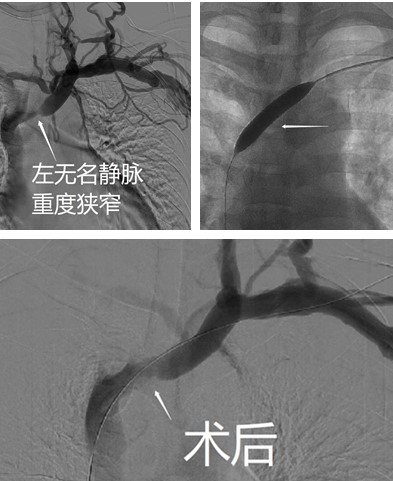

血液透析患者在动静脉内瘘术后会发生手部或上肢肿胀的症状,称为肿胀手综合征。近些年,因越来越多的患者选择动静脉内瘘作为透析通路的治疗手段,肿胀手综合征的病例也相应增加,成为维持性血液透析患者较常见的并发症,同时也是影响血液透析疗效的重要原因。患者王某正是这种情况,因规律血液透析1年,左上肢肿胀半年余,收治我院血液净化中心。术前评估其内瘘短期内存在狭窄加重、血栓形成以及闭塞风险,经过前期与患者的充分沟通、积极准备,我院决定为该患者行球囊扩张成形术。手术由血液净化中心主治医师姜晖与住院医师许若男完成。术后,即刻为患者复查造影,狭窄病变解除,部分因狭窄导致的分支血管消失,手术当日出院,术后第二天随访,患者左上肢肿胀完全缓解。

中心静脉球囊扩张成形术是一种微创诊疗技术,具有创伤小,恢复快的优势,无需外科手术,最大限度地保护血液透析患者最为宝贵的血管资源,避免了血液透析最终“无路可走”的困境。但手术难度高,风险大,对操作医生有较高要求,目前本地区开展较少。